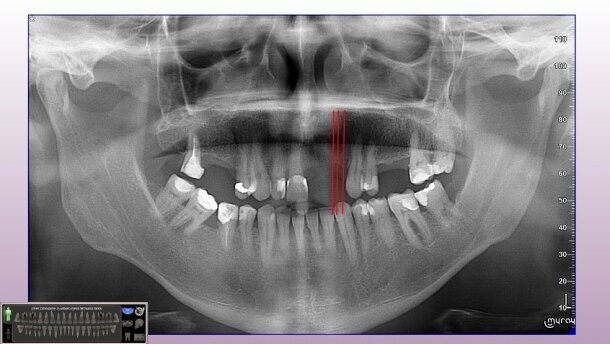

W badaniu klinicznym stwierdzono też wadę zgryzu (zgryz krzyżowy) w pozycji zębów 13, 14. Życzeniem pacjenta było stałe uzupełnienie braków zębowych, jednocześnie pacjent nie wyraził zgody na szlifowanie zębów własnych w celu wykonania mostów. Przeprowadzona analiza radiologiczna (Ryc. 1) potwierdziła możliwości rehabilitacji w oparciu o implantoterapię. Radiologicznie obustronnie w odcinkach bocznych stwierdzono wystarczającą ilość struktury kostnej w wymiarach przestrzennych, a w odcinku przednim pomiary poprzeczne 3DTS (Ryc. 2) uwidoczniły zanik kości szczęki bardzo dużego stopnia. W odcinkach bocznych braki zębowe uzupełniono w oparciu o zastosowanie wszczepów śrub bikortykalnych. W odcinku przednim szczęki z uwagi na bardzo duży zanik tkanki kostnej, z wyboru zastosowano wszczepy igłowe (Ryc. 3).

Po zabiegu implantacji wykonano kontrolne badanie radiologiczne, wizytę zakończono zacementowaniem implantoprotez prowizorycznych, zgodnie z oczekiwaniami pacjenta. Po upływie jednego miesiąca pobrano wyciski w celu wykonania implantoprotez ostatecznych – porcelanowych na podbudowie z metalu (Ryc. 4). Podczas wizyty kontrolnej po 5 miesiącach wykonany pantomogram (Ryc. 5) potwierdził prawidłową pozycję wszczepów oraz prawidłowo przeprowadzoną rehabilitację implantoprotetyczną.